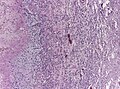

| LM | astrocytic differentiation, nuclear atypia, necrosis, microvascular proliferation, +/-pseudopalisading necrosis |

Microscopic

Features:

- Astrocytic tumour with:

- Nuclear atypia.

- Necrosis.

- Endothelial proliferation (AKA microvascular proliferation).

- +/-"Pseudopalisading necrosis" - tumour cells lined-up like a picket fence around necrotic areas.